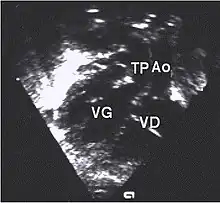

- Les coupes échographiques les plus utiles à cette fin sont :

- la coupe parasternale gauche grand axe : elle montre que le vaisseau issu du ventricule gauche (le plus postérieur) se dirige anormalement vers l'arrière et se bifurque précocement. C'est donc le tronc pulmonaire et non l'aorte comme normalement ;

- les coupes sous costales qui montrent bien le trajet parallèle des gros vaisseaux et leur inversion.